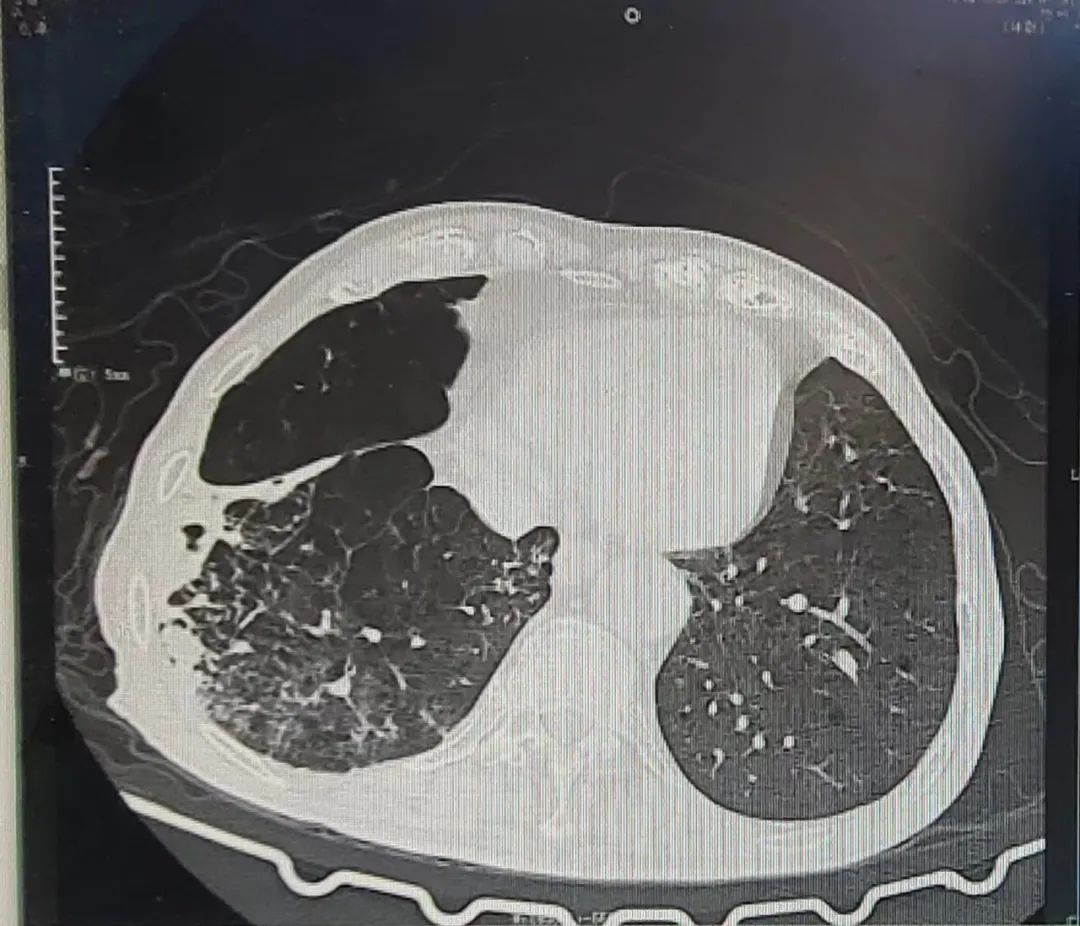

治療前

接診的呼吸危重癥科郭敏主任經(jīng)過一系列的查體后初步判斷已經(jīng)發(fā)展成肺炎了,收治入院后檢查為甲型流感病毒陽性、肺炎支原體陽性、呼吸道合胞病毒陽性、白色念珠菌感染,1型呼吸衰竭,心力衰竭,奇異變形桿菌感染,胸部CT顯示,劉爺爺?shù)挠曳蜗氯~已變白。

治療后

郭主任及團隊給予吸氧、抗感染、止咳化痰平喘,抗病毒,強心利尿、抗真菌治療,劉爺爺目前的癥狀已經(jīng)明顯好轉(zhuǎn)出院。

“白肺”患者的肺組織肉眼下看并不是白色的,而是拍出的片子,在本應(yīng)呈現(xiàn)黑色的肺部區(qū)域呈現(xiàn)出異常的白色顯像。正常情況下,肺部主要是由充滿了空氣的肺泡組成,進行CT或者是X線檢查時,射線可以很容易地穿透肺泡,在影像學上顯示為黑色區(qū)域。當肺部受到病原體感染、臨床上表現(xiàn)為重型肺炎時,患者肺泡里會出現(xiàn)炎癥、滲出或?qū)嵶儠r,射線不容易穿透病變區(qū)域,在影像學就出現(xiàn)了白色的區(qū)域。當白色區(qū)域面積達到了70%-80%時,臨床上俗稱其為“白肺”。